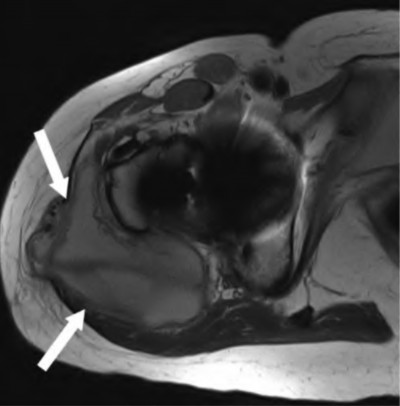

A 75-year-old man underwent total hip arthroplasty 10 years ago. He now reports mild groin pain which has been increasing lately. What is the most likely explanation for the finding in Figure A indicated with the arrows?

Osteolysis of the pelvis is a common complication associated with total hip arthroplasty. Osteolysis affects sockets with and without cement, and has been attributed to the biologic reaction to wear debris. With well-fixed cementless sockets, an expansile pattern of osteolysis is usually seen.

The radiographic appearance has a radiolucent area that starts at the implant-bone interface and expands into the cancellous bone away from the implant.

This pattern of osteolysis can be explained with the concept of effective joint space. This concept states that joint fluid and wear particles will flow according to pressure gradients and follow the path of least resistance.

The Level 5 review article by Chiang discusses osteolysis in further depth.